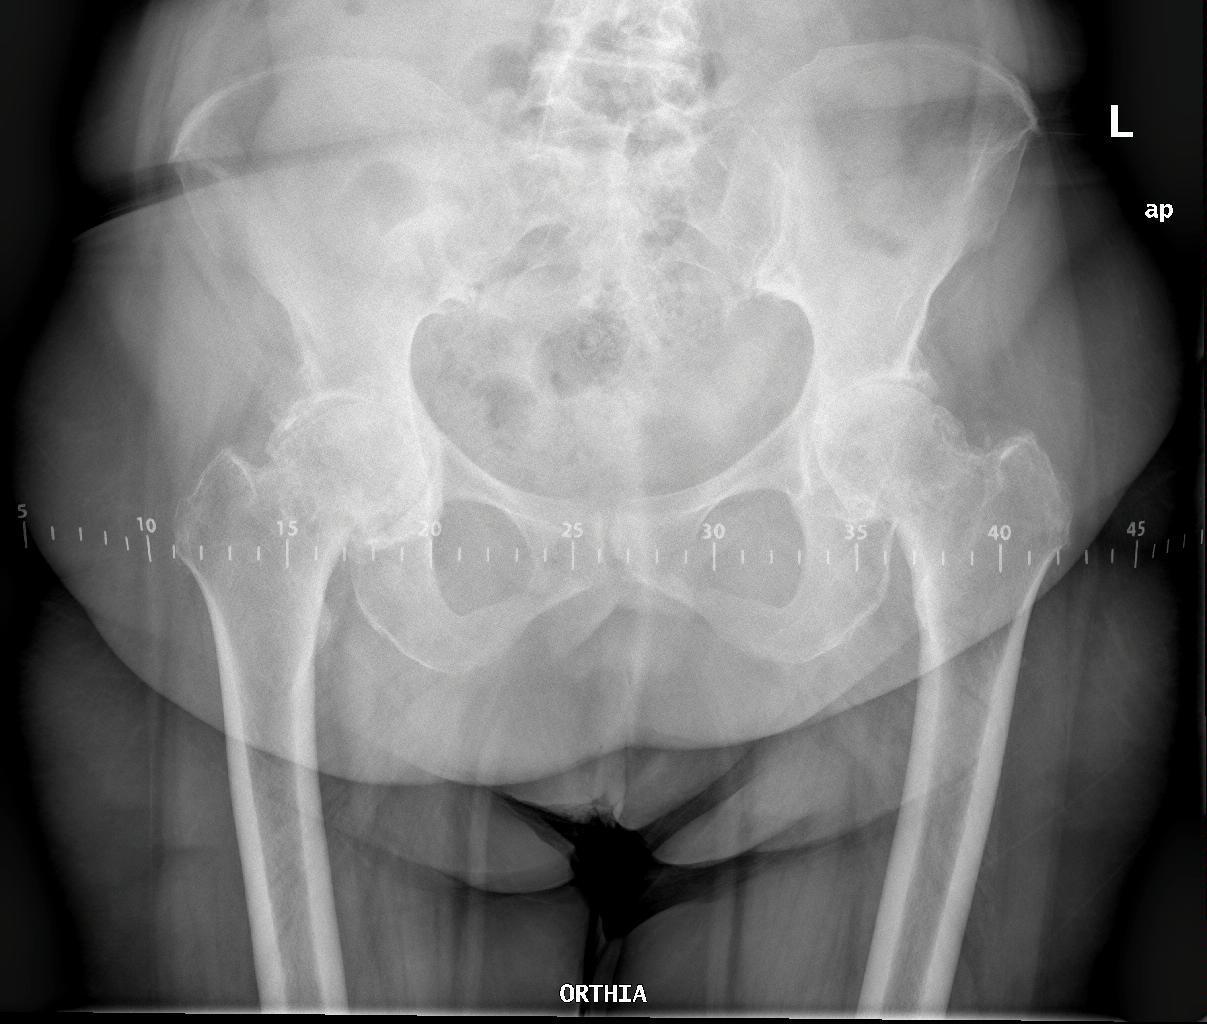

Το πρώτο βήμα κατά τη λήψη της απόφασης για την αντικατάσταση ισχίου είναι να συναντήσετε τον χειρουργό σας για να δείτε εάν είστε υποψήφιος για χειρουργική επέμβαση ολικής αρθροπλαστικής ισχίου. Ο χειρουργός σας θα πάρει το ιατρικό ιστορικό σας, θα κάνει μια φυσική εξέταση και θα ζητήσει ακτινογραφία του ισχίου σας. Ακόμα κι αν ο πόνος είναι έντονος και οι ακτινογραφίες δείχνουν προχωρημένη αρθρίτιδα της άρθρωσης, η πρώτη γραμμή θεραπείας είναι σχεδόν πάντα μη χειρουργική. Αυτό περιλαμβάνει απώλεια βάρους εάν χρειάζεται, πρόγραμμα άσκησης, αντιφλεγμονώδη φάρμακα, ενέσεις ή νάρθηκες. Εάν τα συμπτώματα συνεχιστούν παρά αυτές τις θεραπείες και με επιβεβαιωτικές ακτινογραφίες, τότε μπορείτε να εξετάσετε το ενδεχόμενο χειρουργικής επέμβασης.

Τα περισσότερα εμφυτεύματα σήμερα έχουν παρόμοια σχέδια και σχήματα, αλλά ο γιατρός σας θα καθορίσει ποια σχέδια λειτουργούν καλύτερα για το σώμα σας. Αυτά τα εμφυτεύματα είναι κατασκευασμένα από κοβάλτιο χρώμιο ή τιτάνιο. Μια μεταβλητή που παραμένει ακόμα είναι η επιφάνεια φόρτισης. Η επιφάνεια φόρτισης είναι η σφαίρα, η κεφαλή και η επένδυση που προσκολλώνται στο μηριαίο στέλεχος, και το κυπέλιο, η το κοτυλιαίο εμφύτευμα που στερεώνεται στο οστό. Η κεφαλή μπορεί να αποτελείται είτε από μέταλλο (κράμα χρωμίου κοβαλτίου) είτε από κεραμικό και η επένδυση μπορεί να είναι από πλαστικό (πολυαιθυλένιο), μέταλλο ή κεραμικό. Η κεφαλή και η επένδυση μπορούν στη συνέχεια να χρησιμοποιηθούν σε διαφορετικούς συνδυασμούς και ονομάζονται για τον αντίστοιχο συνδυασμό επένδυσης κεφαλή (μέταλλο σε πολυ, κεραμικό σε πολυ, κεραμικό σε κεραμικό κ.λπ.).